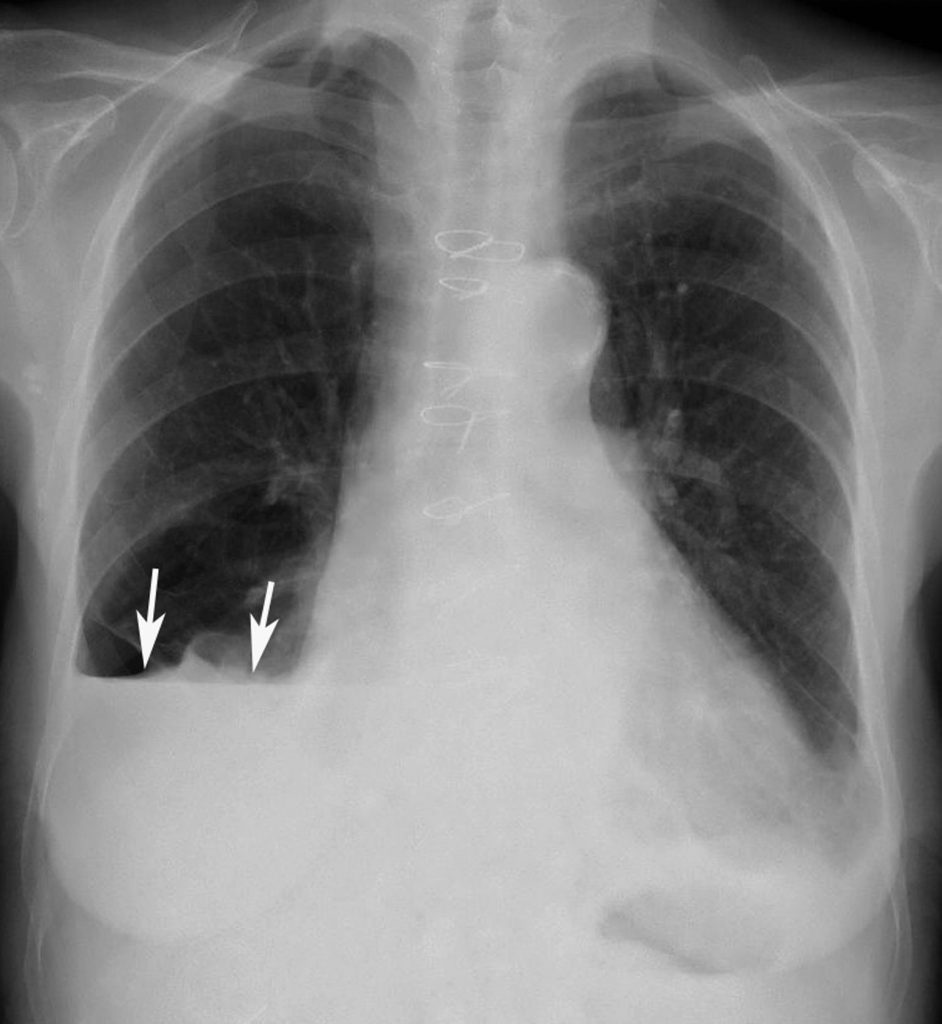

L’épanchement mixte gazeux et liquidien, ou hydropneumothorax, est identifié par la présence d’un niveau hydroaérique en position debout (figure 98.4). Un hydropneumothorax est la conséquence d’une plaie pénétrante ou d’une fistule bronchopleurale.

Fig. 98.4. Cliché en position debout. Hydropneumothorax droit ; présence d’un niveau horizontal hydroaérique.

Source : CERF, CNEBMN, 2022.